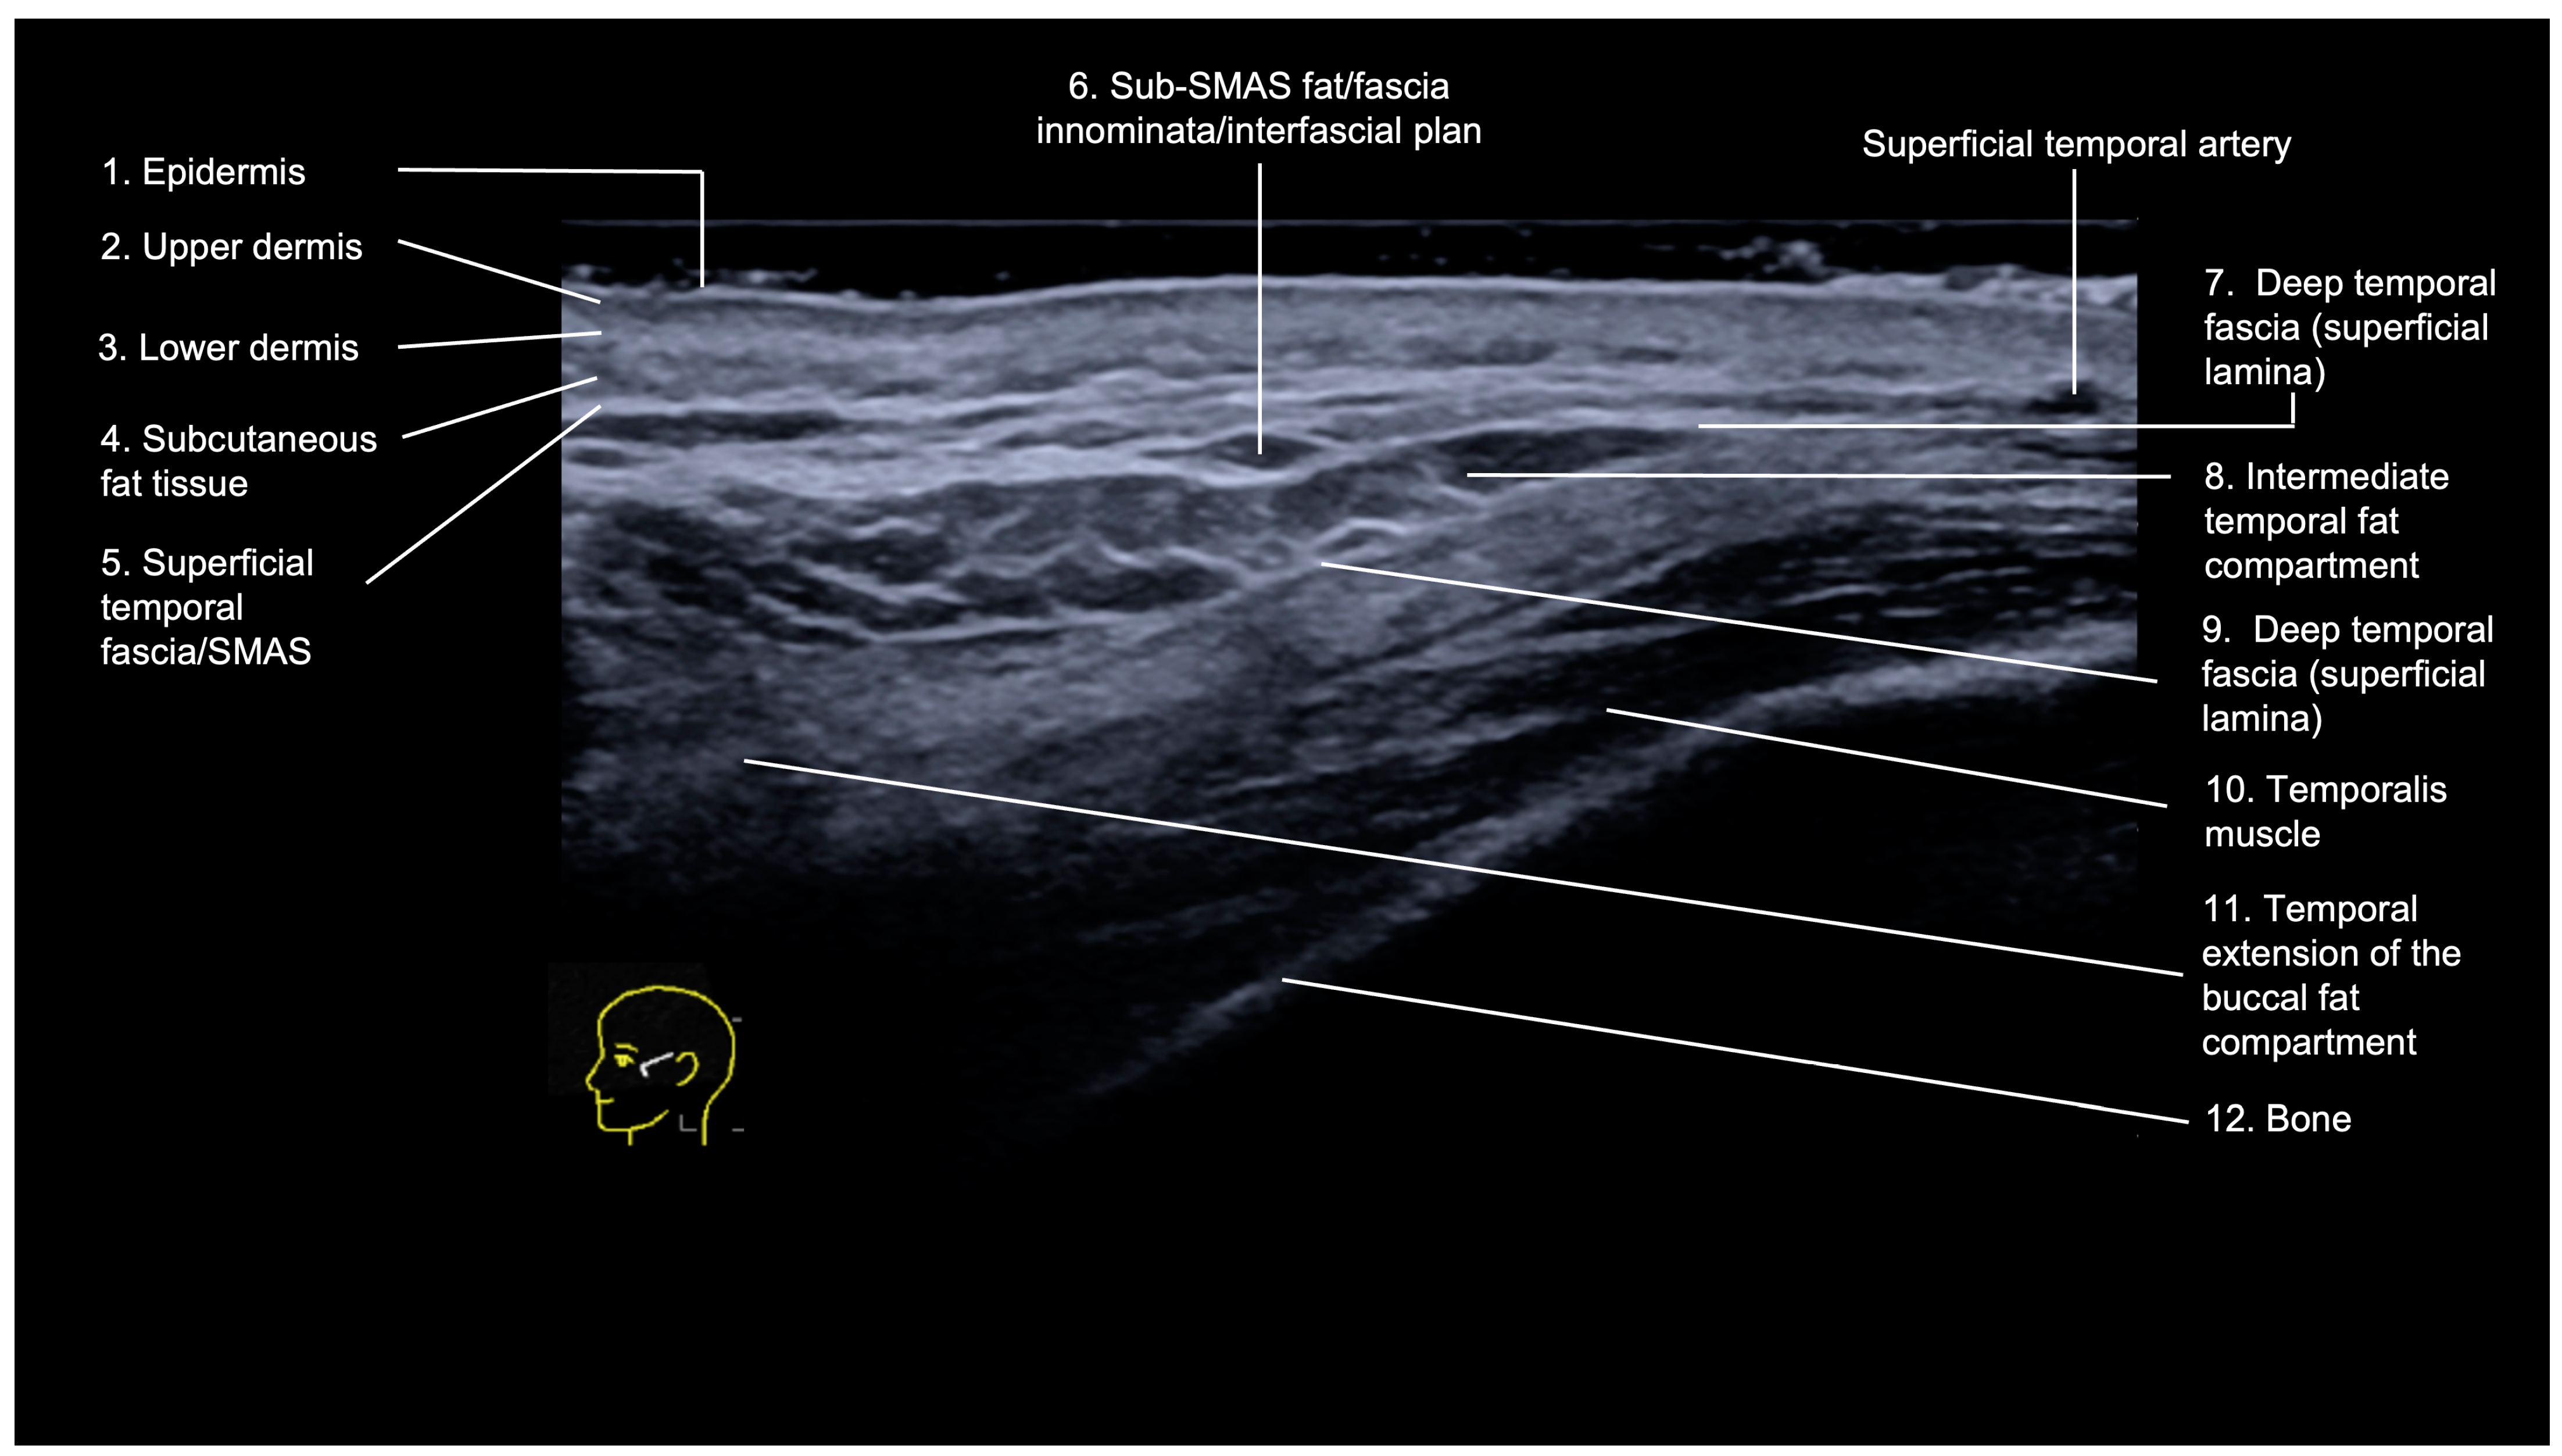

3.1.1. Sonographic Anatomy

- Epidermis: hyperechoic line.

- Upper dermis: hypoechoic homogeneous layer.

- Lower dermis: usually more echogenic layer than the upper dermis.

- Subcutaneous fat tissue: a hypoechoic layer composed of fat lobules and hyperechoic septae.

- Superficial temporal fascia/Superficial musculoaponeurotic system (SMAS): linear hyperechoic layers enveloping the superficial temporal artery and vein.

- Sub-SMAS fat: also called innominate fascia, it is a hypoechoic layer composed of loose connective tissue and fat lobules. This is the interfascial plane.

- Superficial lamina of the deep temporal fascia: a hyperechoic line, which is juxtaposed to the intermediate temporal fat compartment.

- Intermediate fat compartment (loose areolar tissue): a hypoechoic triangular layer composed of fat lobules and hyperechoic septae. The middle temporal vein can be encountered in this layer.

- Deep lamina of the deep temporal fascia: a hyperechoic line, which is deep to the intermediate temporal fat compartment.

- Temporal muscle: a large hypoechoic structure above the bone, where the anterior and posterior deep temporal arteries are located.

- Temporal extension of the buccal fat compartment: a hypoechoic fat compartment adjacent to the lateral orbital rim, connected to the buccal fat pat. Easily recognized when patient is asked to open and close the mouth, this fat pad can be found under the deep lamina of the deep temporal fascia.

- Bone: a thin hyperechoic line with acoustic shadowing.